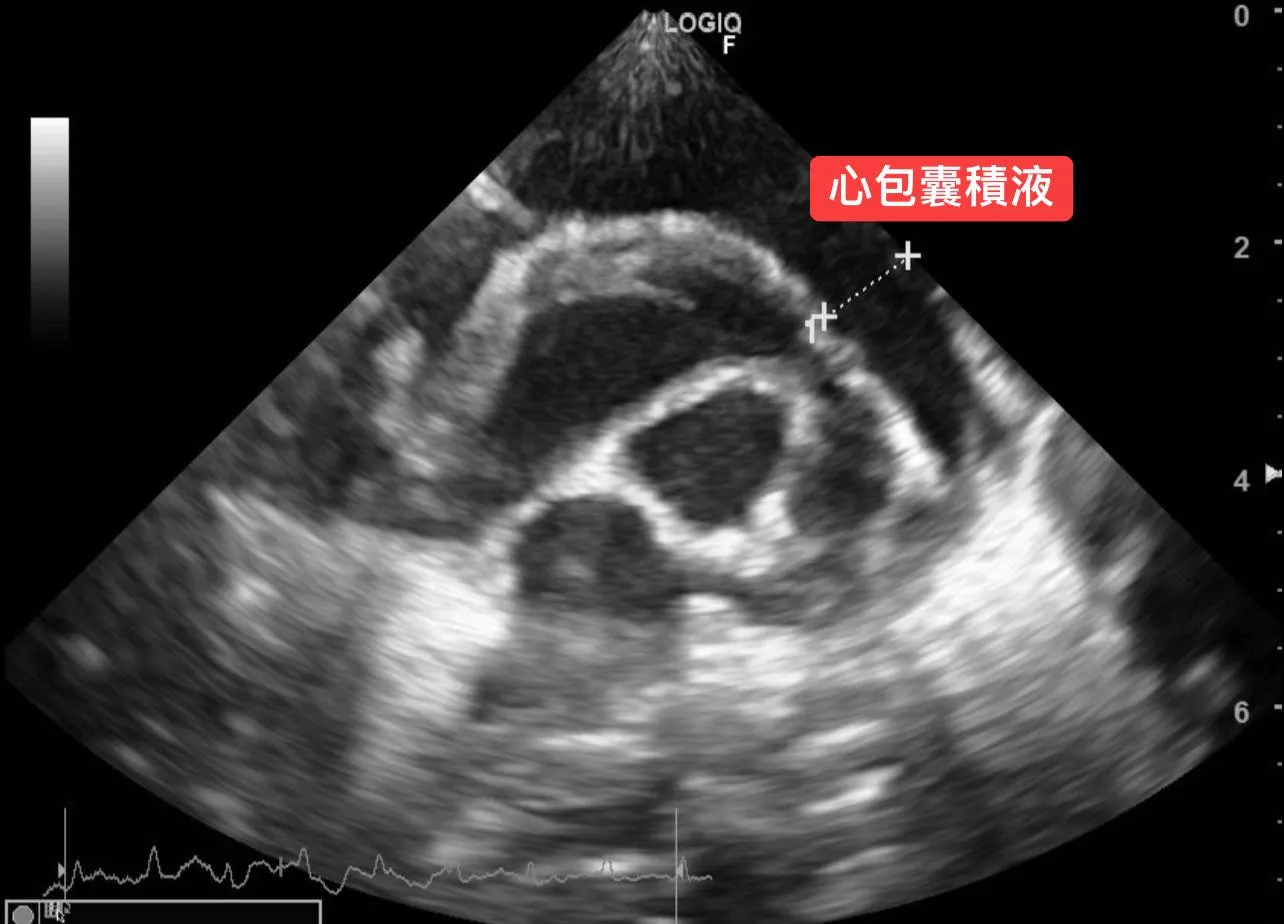

病例分享 毛孩的臨床症狀 1. 突然變很喘,伴隨間斷性劇烈咳嗽。 2. 精神食慾正常,於友院服用止咳藥物後,無顯著改善。 3. 腹部異常膨脹,於

當遇到毛孩有呼吸急促、會喘、咳嗽、呼吸困難等狀況時,安可的醫師腦海裡其實已經開始思考所有可能的原因,例如: 心臟問題、肺臟問題、胸膜腔壓迫性疾病、疼痛,抑或是其他生理性等問題,都一一跑過